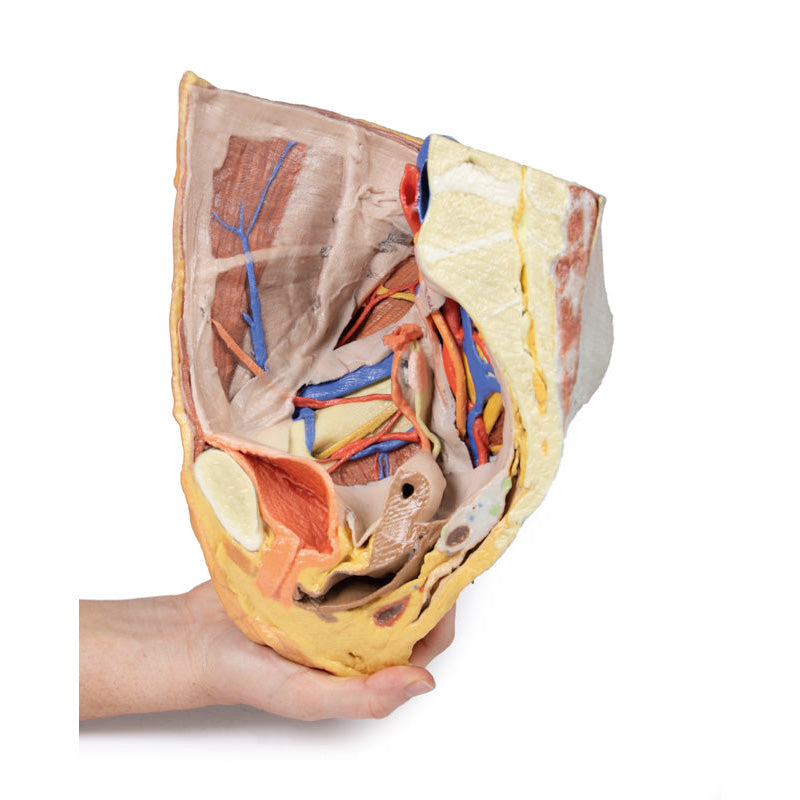

3D Printed Female right pelvis superficial and deep structures

The specimen has been sectioned transversely through the L4 vertebra, displaying a cross section of the colon, the epaxial musculature (psoas and quadratus lumborum muscles), and the abdominal wall musculature. The common iliac artery has been preserved from the level of the L4 vertebra, and its bifurcation into the external and internal iliac arteries can be observed at the level of the sacral promontory. Deep to the arteries the common iliac vein and the origin of the inferior vena cava are visible.

The external iliac artery and vein passes anteroinferiorly along the pelvic brim, giving rise to the inferior epigastric and deep circumflex arteries and veins before passing deep to the inguinal ligament. The psoas major muscle lies lateral to the external iliac artery, with the femoral nerve evident on its lateral margin close to the inguinal ligament. The lateral cutaneous nerve of the thigh travels laterally on the superficial surface of the iliacus muscle to exit the ‘false’ pelvis close to the anterior superior iliac spine.

Following the course of the internal iliac artery deep to the undissected peritoneum, many of the major branches of its anterior and posterior divisions can be identified. The anterior division divides (deep to the peritoneum) into the superior vesical, obturator and obliterated umbilical artery. With a course parallel to the obturator artery, the obturator nerve can be seen running over obturator internus before entering the obturator canal together with the obturator vein (nerve, artery, vein in that order from superior to inferior).

Branches of the posterior division of the internal iliac artery, iliolumbar, and several lateral sacral arteries, can be seen arising from the posterior aspect of the internal iliac just below the sacral promontory. Its terminal branch, the superior gluteal, usually passes posteriorly between the lumbosacral trunk and S1 nerve, but this is hidden from view. The internal iliac vein and its tributaries - the obturator veins, uterine vein, vesical veins, etc. can be seen lying internal to the nerves and muscles. The large S1 and S2 roots and the smaller S3 nerve root can be seen emerging from the sacral foramina to pass laterally where it is joined by the lumbosacral trunk (L4 and l5 roots) which is not visible, to form the sciatic nerve which exits through the greater sciatic foramen to emerge on the posterior aspect in the gluteal region. In the pelvis as these roots pass laterally they are interdigitated between the fibres of piriformis muscle.

The right ureter can be clearly seen as it passes inferiorly on the posterior abdominal wall superficial to psoas muscle. It passes over the pelvic brim at the bifurcation of the common iliac artery to descend on the lateral wall of the pelvis before passing medially in the base of the broad ligament (hidden from view as the peritoneal folds that ‘drape’ over the uterine [Fallopian] tubes are still intact) to reach the lateral angles of the bladder. In the pelvis the viscera which lies most anteriorly is the bladder. Its thick wall and cavity is easily seen in this mid-sagittal cut. Indeed the ureteric orifice can be seen at the angle of the trigone of the bladder on its internal mucosal surface. The relations of the uterus to the vagina are clearly visible in the mid-sagittal section. Indeed the anterior and posterior fornices are clearly seen as is the os of the cervix. The round ligament of the uterus has been removed along with some peritoneum to display the structures in the lateral pelvic wall. The entire right Fallopian tube is identifiable as it passes from the lateral aspect of the body of the uterus to terminate as the fimbria which overhangs the right ovary which is still held in place by its mesovarium. The ovary is attached laterally to the pelvic brim by the suspensory ligament of the ovary (sometimes called the infundibulopelvic ligament) which contains its named artery and veins. The ligament of the ovary is clearly visible leading from the medial aspect of the ovary to the lateral surface of the uterus.

There are only small cut surfaces of the rectum (visible as little islands of mucosa) visible on the sagittal cut surface suggesting that it is slightly off the midline plane. Some pararectal lymph nodes (coloured pale green) can be seen close to these islands of rectal mucosa. On the anterior aspect of the 3D print the inguinal ligament has been retained and deep to it the femoral artery, vein and nerve pass to the anterior compartment of the thigh.

In the gluteal region (note the femur has been removed to expose the acetabulum) the sciatic nerve can be seen emerging from the greater sciatic foramen (GSF) alongside the inferior gluteal vessels below the remains of the piriformis fibres, whereas the superior gluteal vessels and nerve emerges above the piriformis. Below these vessels the pudendal nerves and vessels can be seen exiting the GSF and passing over the sacrospinous ligament to enter the lesser sciatic foramen, thereby entering the perineum along the lateral wall of the ischioanal fossa.

3D Printed Female right pelvis superficial and deep structures

This 3D printed female right pelvis preserves both superficial and deep structures of the true and false pelves, as well as the inguinal ligament, the obturator membrane and canal, and both the greater and lesser sciatic foramina. Somewhat unique is the removal of portions of the peritoneum (a grayish colour) to create ‘windows’ displaying extraperitoneal structures.The specimen has been sectioned transversely through the L4 vertebra, displaying a cross section of the colon, the epaxial musculature (psoas and quadratus lumborum muscles), and the abdominal wall musculature. The common iliac artery has been preserved from the level of the L4 vertebra, and its bifurcation into the external and internal iliac arteries can be observed at the level of the sacral promontory. Deep to the arteries the common iliac vein and the origin of the inferior vena cava are visible.

The external iliac artery and vein passes anteroinferiorly along the pelvic brim, giving rise to the inferior epigastric and deep circumflex arteries and veins before passing deep to the inguinal ligament. The psoas major muscle lies lateral to the external iliac artery, with the femoral nerve evident on its lateral margin close to the inguinal ligament. The lateral cutaneous nerve of the thigh travels laterally on the superficial surface of the iliacus muscle to exit the ‘false’ pelvis close to the anterior superior iliac spine.

Following the course of the internal iliac artery deep to the undissected peritoneum, many of the major branches of its anterior and posterior divisions can be identified. The anterior division divides (deep to the peritoneum) into the superior vesical, obturator and obliterated umbilical artery. With a course parallel to the obturator artery, the obturator nerve can be seen running over obturator internus before entering the obturator canal together with the obturator vein (nerve, artery, vein in that order from superior to inferior).

Branches of the posterior division of the internal iliac artery, iliolumbar, and several lateral sacral arteries, can be seen arising from the posterior aspect of the internal iliac just below the sacral promontory. Its terminal branch, the superior gluteal, usually passes posteriorly between the lumbosacral trunk and S1 nerve, but this is hidden from view. The internal iliac vein and its tributaries - the obturator veins, uterine vein, vesical veins, etc. can be seen lying internal to the nerves and muscles. The large S1 and S2 roots and the smaller S3 nerve root can be seen emerging from the sacral foramina to pass laterally where it is joined by the lumbosacral trunk (L4 and l5 roots) which is not visible, to form the sciatic nerve which exits through the greater sciatic foramen to emerge on the posterior aspect in the gluteal region. In the pelvis as these roots pass laterally they are interdigitated between the fibres of piriformis muscle.

The right ureter can be clearly seen as it passes inferiorly on the posterior abdominal wall superficial to psoas muscle. It passes over the pelvic brim at the bifurcation of the common iliac artery to descend on the lateral wall of the pelvis before passing medially in the base of the broad ligament (hidden from view as the peritoneal folds that ‘drape’ over the uterine [Fallopian] tubes are still intact) to reach the lateral angles of the bladder. In the pelvis the viscera which lies most anteriorly is the bladder. Its thick wall and cavity is easily seen in this mid-sagittal cut. Indeed the ureteric orifice can be seen at the angle of the trigone of the bladder on its internal mucosal surface. The relations of the uterus to the vagina are clearly visible in the mid-sagittal section. Indeed the anterior and posterior fornices are clearly seen as is the os of the cervix. The round ligament of the uterus has been removed along with some peritoneum to display the structures in the lateral pelvic wall. The entire right Fallopian tube is identifiable as it passes from the lateral aspect of the body of the uterus to terminate as the fimbria which overhangs the right ovary which is still held in place by its mesovarium. The ovary is attached laterally to the pelvic brim by the suspensory ligament of the ovary (sometimes called the infundibulopelvic ligament) which contains its named artery and veins. The ligament of the ovary is clearly visible leading from the medial aspect of the ovary to the lateral surface of the uterus.

There are only small cut surfaces of the rectum (visible as little islands of mucosa) visible on the sagittal cut surface suggesting that it is slightly off the midline plane. Some pararectal lymph nodes (coloured pale green) can be seen close to these islands of rectal mucosa. On the anterior aspect of the 3D print the inguinal ligament has been retained and deep to it the femoral artery, vein and nerve pass to the anterior compartment of the thigh.

In the gluteal region (note the femur has been removed to expose the acetabulum) the sciatic nerve can be seen emerging from the greater sciatic foramen (GSF) alongside the inferior gluteal vessels below the remains of the piriformis fibres, whereas the superior gluteal vessels and nerve emerges above the piriformis. Below these vessels the pudendal nerves and vessels can be seen exiting the GSF and passing over the sacrospinous ligament to enter the lesser sciatic foramen, thereby entering the perineum along the lateral wall of the ischioanal fossa.